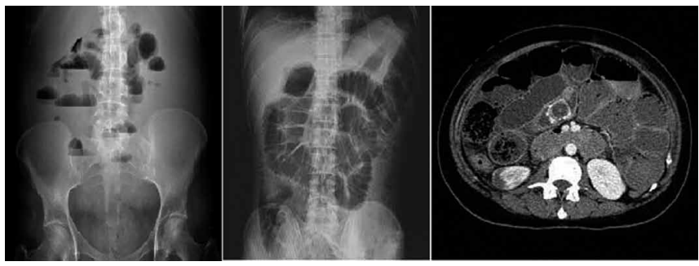

Um homem de 66 anos, com histórico de três laparotomias prévias por cirurgias abdominais há mais de 10 anos, apresenta dor abdominal difusa, náuseas, vômitos biliosos e ausência de evacuação há 48 horas. No exame físico, o abdome está distendido, com ruídos hidroaéreos metálicos. Após ressuscitação volêmica realizada no pronto atendimento, o paciente é internado para continuidade do tratamento. A radiografia simples de abdome e tomografia computadorizada (TC) do abdome estão demonstradas a seguir.

Com base no caso clínico e na radiografia apresentados, assinale a alternativa que indica a conduta mais apropriada nesse caso.